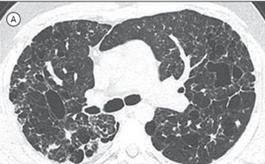

Imagem 2: Síndrome de Birt-Hogg-Dubé